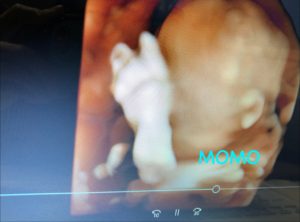

いつもの産院よりも鮮明に見える胎児がとても可愛く見えました。

エコーでは元気に私のお腹を蹴ったりずっと動き回っている赤ちゃんが、とても愛おしくさようなら出来なくなりそうな気持ちもあったのです。